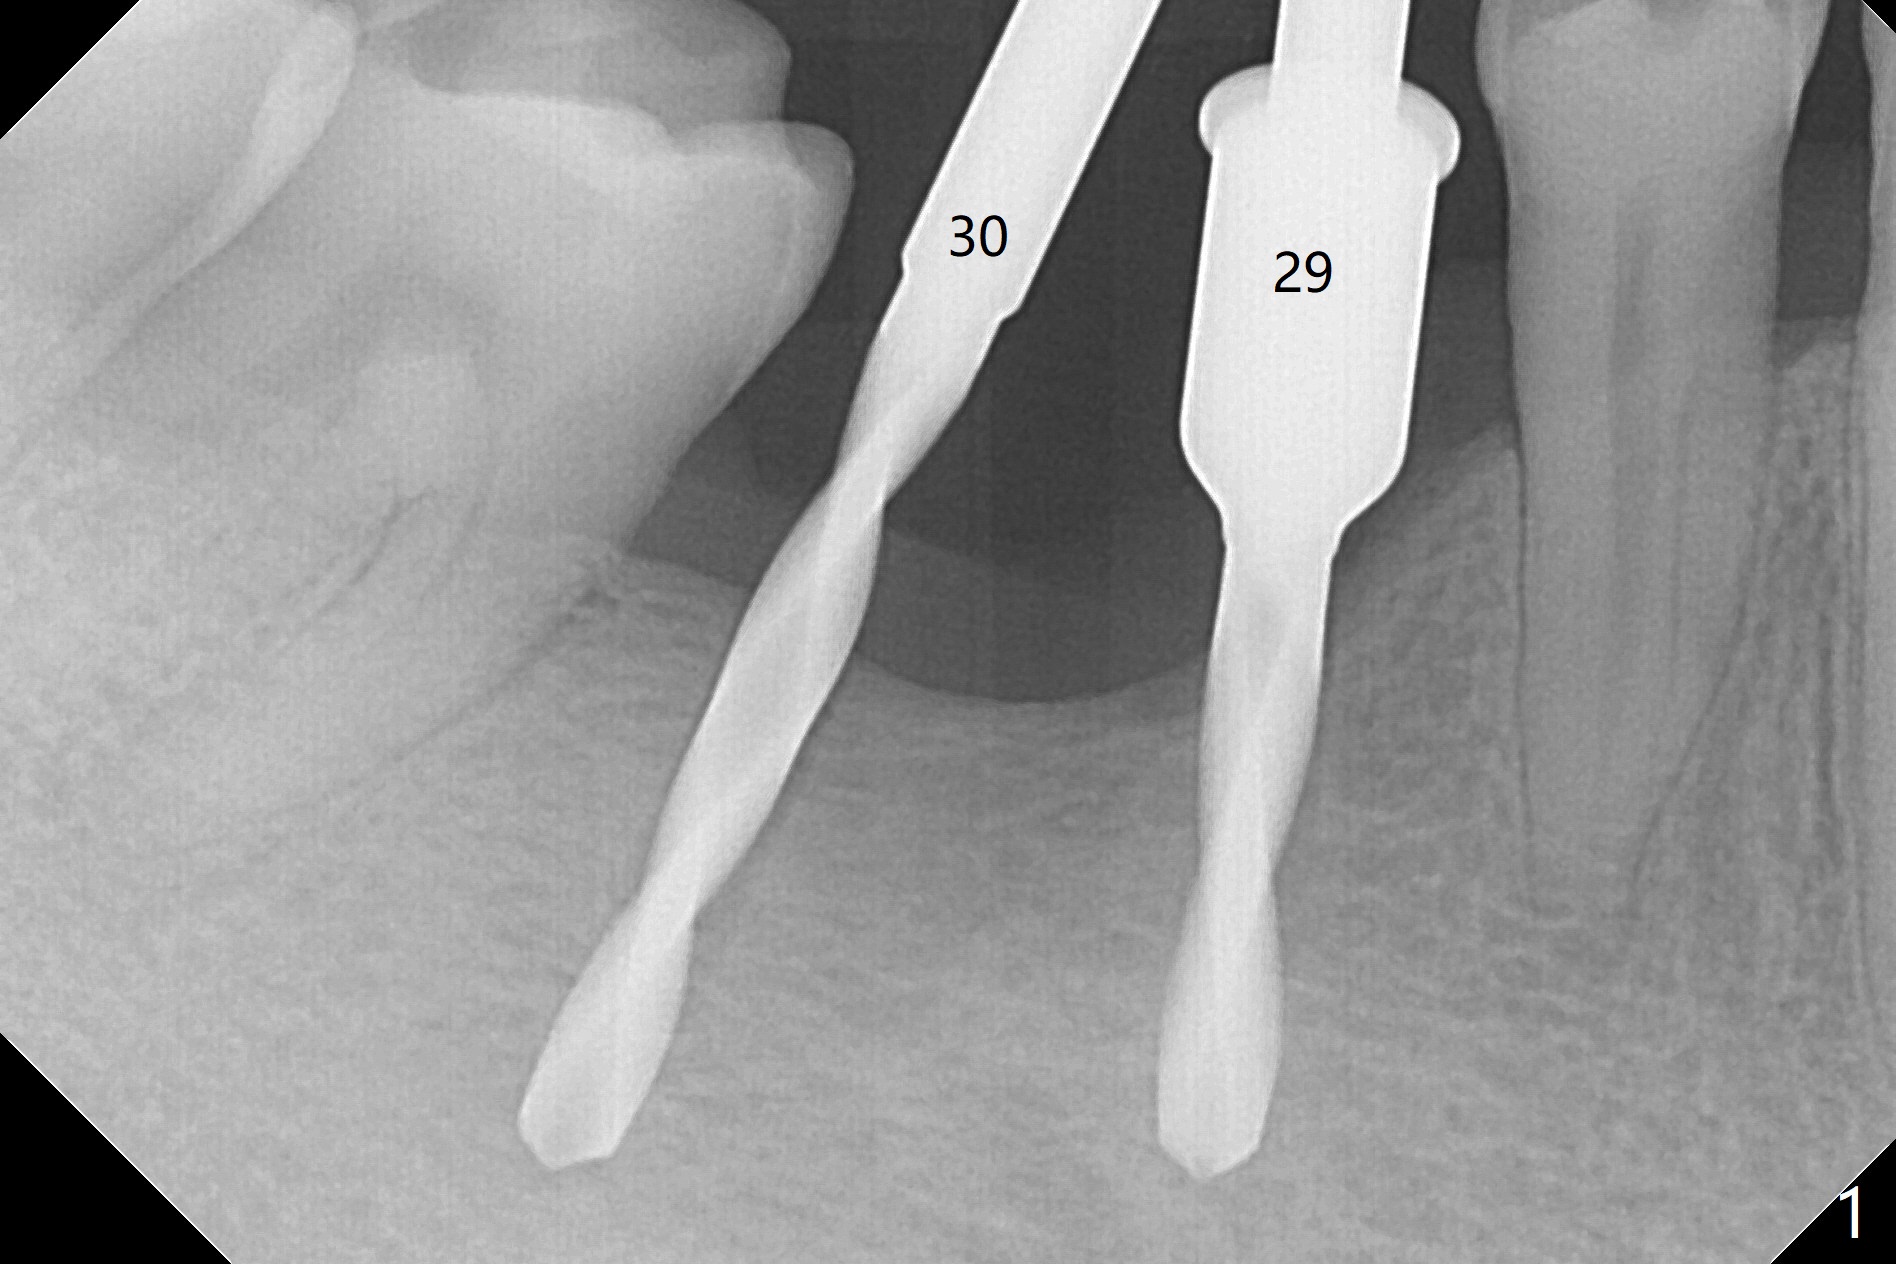

After initial osteotomy using 2.2 mm drill for 10 and 11.5 mm at #29 and 30, respectively, the guide is removed for re-insertion of drills and PA (Fig.1). The osteotomy at #29 is found lingually and in the nonkeratinized gingiva with mild laceration (wish incision to be made before osteotomy); the osteotomy is established a little lingual at #29 (Fig.2) and more or less in the middle of the narrow ridge and #30 (Fig.3). Lindamann bur is used to move #29 osteotomy buccally. A 1.5 mm drill is used to increase the depth free hand before placement of 2.5x10(4) mm 1-piece implants (Fig.4). After adjustment of the implant depth (Fig.5), CT is retaken, which shows proper implant placement (Fig.6,7). Probably due to good oral hygiene, the gingiva around the implants appears to be keratinized 4 months postop (Fig.8). After abutment preparation for margin and parallelism, impression is taken (Fig.9). When the permanent crowns are temporarily cemented, the large gingival embrasure is noted (Fig.10,11). The latter could be reduced by modifying the provisional in the healing stage. In fact the crown at #29 dislodges 2 days post cementation because lingual (Fig.12) and distal (Fig.13) placement. A surgical stent should have been fabricated from RPD for free hand placement!